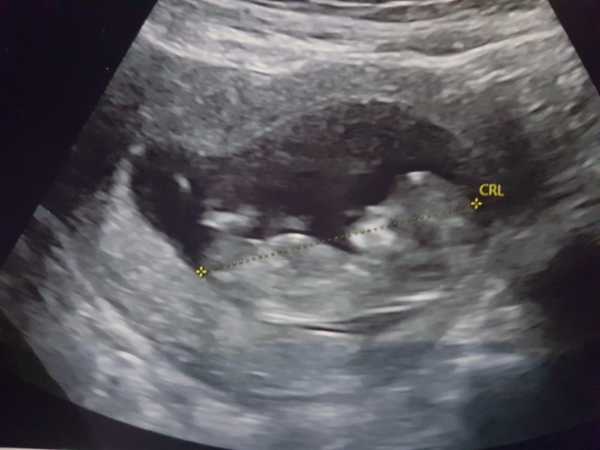

I updated my other thread, but it turns out baby is absolutely fine and measuring 12+0!

I had a scan today and everything is ticking along. They brought me forward a few days based on the measurement. Felt pretty crazy seeing it moving around on the screen having grown from a beating blob in my 6 week scan.

@SurfingOwl I meant to ask, but the question was on the tip of my tongue when the sonographer said "I can see baby!" So I promptly forgot. It wasn't even an internal scan. My midwife had said "a 12 week baby should pop up as soon as the probe touches you", which this did. So it just makes me think that she had no idea what she was doing.

I missed out on a lot -what a relief for you @Firstbornunicorn and what a total farce. Scan looking good! Having had a series of paranoid scans across my two MCs and this one, I can say that the quality of the machines varies greatly and there is no doubt the best scan I had was private in London (I'm from the southwest and we have poor machines down here in comparison).

I had my scan this morning. They moved my dates forward a whole week, now I’m 13+5 due on 27 April. As this thread is May-ish, am I ok to stay?